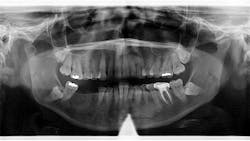

A panoramic radiograph revealed an almost-vague radiodense lesion on the lower left side, around the apices of teeth nos. 20–22, measuring approximately 3 cm x 1.5 cm. The lesion was nonpalpable, the area was not tender to palpation, and the patient was unaware of its presence.

Definitive diagnosis: Idiopathic osteosclerosis

Since this patient presented with no neurosensory changes, cortical expansion or displacement or resorption of adjacent teeth, and its cause could not be readily explained, it is consistent with a diagnosis of idiopathic osteosclerosis. The patient continues to be recalled periodically to assess for changes in this area.